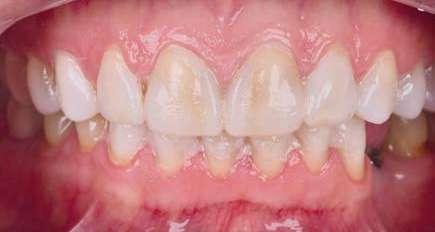

Presentación del caso clínico

A continuación, presentamos el caso clínico de una paciente con unos dientes mal posicionados y con una coloración acentuada sobre todo a nivel de los centrales que además presentaban extensas restauraciones antiguas de composite en interproximal cerrando diastemas que originalmente presentaba la paciente. Estos dientes necesitarán tener una preparación un poco más subgingival y también removido previamente todo el composite antiguo con el objetivo de camuflar este cambio de color y evitar zonas visiblemente no estéticas.

Además, lo combinaremos con unas carillas inyectadas inferiores también planificadas digitalmente y sin tallado, para crear una armonía y equilibrio con la parte superior.

1 Inicio.

Como podemos observar la paciente tenía un sustrato muy desfavorable, con un color aproximado de A3,5 Vita.

Para la arcada inferior se optó por unas carillas inyectadas, completamente respetuosas con los tejidos, que nos permiten mejorar la apariencia de los dientes y dar así una mayor armonía con la parte superior. Al ser también planificadas digitalmente aseguramos que lo que colocamos en boca sea una fiel reproducción del diseño previamente aceptado por el paciente y el profesional.

caso clínicoODONTOLOGÍA ESTÉTICA 30 eldentistamoderno noviembre/diciembre 2022

Mockup.

En la arcada superior por el contrario se decidió poner unas carillas de disilicato para poder cubrir las expectativas de la paciente y ajustar el color al que ella deseaba, bajando casi en 5 tonos el color final. Se planificaron preparaciones digitales conservadoras.

La tecnología digital permite lograr el equilibrio de espesores ideal para cada caso, así como un eje de inserción adecuado. Todo esto permite dar una garantía de longevidad a las restauraciones planificadas.

En este caso se realizó una preparación previa a la preparación guiada en los márgenes y zonas interproximales, para camuflar el sustrato y dar una correcta inserción; y posteriormente se utilizaron unas guías de tallado diseñadas digitalmente para obtener los resultados precisos y predecibles que requería el caso.

La preparación previa junto a la preparación guiada, resultaron en un equilibrio ideal para los espesores mínimos que requería el caso. Se realizó una prueba en seco para valorar el ajuste final de las restauraciones.

Para cementar las carillas y evitar movimientos no controlados y una incorrecta cementación, utilizaremos una guía de posicionamiento simultáneo, esta guía no es de cementación en bloque ya que las carillas están perfectamente individualizadas. Únicamente sirven para llevar a la boca del paciente las carillas y cementarlas de una forma 100% segura, evitando el estrés que genera un posible movimiento durante la cementación y acelerando los tiempos de trabajo.

Consiguiendo así una perfecta adaptación de los márgenes de las restauraciones y la sensación de naturalidad e integración que se observa en la imagen final.

Como se puede observar en la imagen comparativa, la planificación se reproduce de una forma fiel a lo que se había planificado y aceptado por la paciente. Por tanto, no es una técnica susceptible al operador, que se realiza controlando mucho mejor los tiempos y los resultados obtenidos.